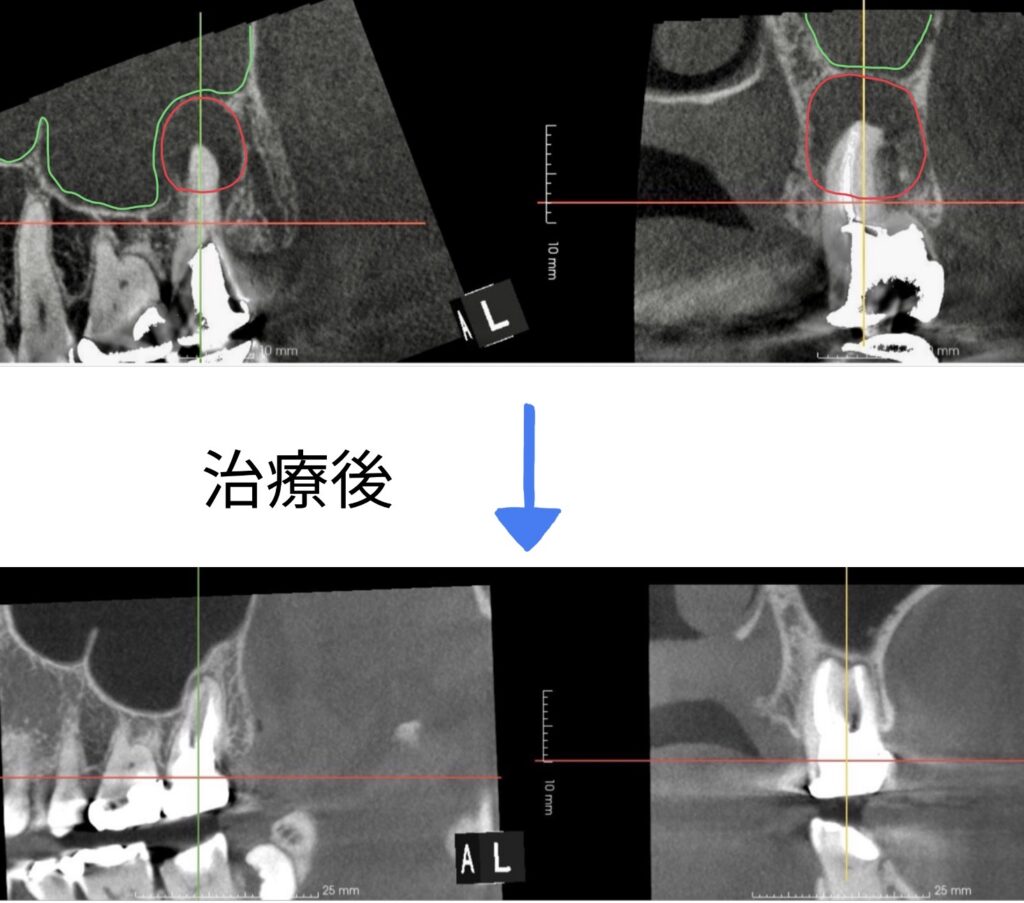

上顎洞にまで及ぶ炎症を主訴に来院された患者さまの術後経過をご紹介します。

治療後の経過は非常に良好で、レントゲン上でも炎症の消失が確認できました。さらに、患者さまご自身の自覚症状としても痛みはなく、快適にお過ごしいただいています。